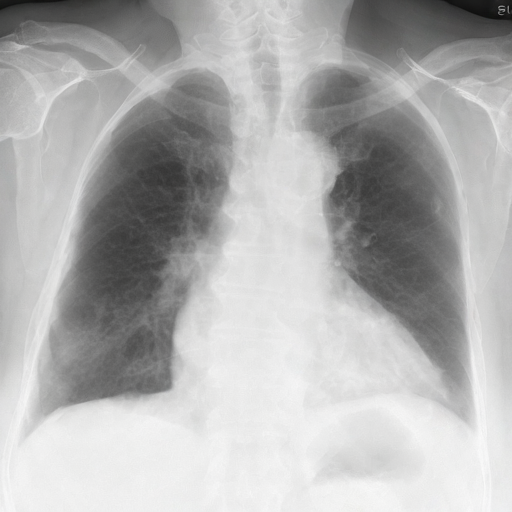

Let's load an example image of a patient with influenza.

For this example, we will remove the visual appearance of influence from the lungs, while preventing changes from happening to the rest of the image. To do this, we create a mask of the lung regions and use this as the edit_mask which defines the region we wish the editing prompt to be applied to. Since we want the rest of the image to remain unchanged, we use the inverse as the keep_mask which defines the region where edits are discouraged from taking place.

from PIL import ImageOps

edit_mask = lung_mask

keep_mask = ImageOps.invert(lung_mask)

torch.manual_seed(1234)

prompt = 'No acute cardiopulmonary process'

edited = radedit_pipeline(

prompt,

weights=[7.5],

image=input_image,

edit_mask=edit_mask,

keep_mask=keep_mask,

num_inference_steps=200,

invert_prompt='',

skip_ratio=0.3,

output_type="pil",

)